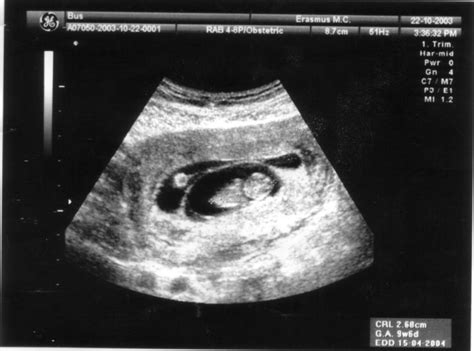

Wanneer je een echo krijgt rond de 6 weken zwangerschap, wordt dit een vroege vitaliteitsecho genoemd. Hoewel deze echo meestal pas bij 7 of 8 weken wordt uitgevoerd, kan een vroege echo waardevolle informatie verschaffen. De echoscopist beoordeelt via een inwendige echo of er een levend vruchtje in de baarmoeder aanwezig is en of de innesteling goed is verlopen.

Aan het begin van de zesde week is de kans klein dat het hartje van het embryo al zichtbaar is. Echter, tegen het einde van de week neemt deze kans toe. Zodra een kloppend hartje wordt waargenomen, is de kans op een miskraam aanzienlijk kleiner. Toch is het ook bij 6 weken zwangerschap mogelijk dat er nog geen hartactiviteit te zien is.

Hoewel het embryo in deze fase nog klein is, is het meestal al zichtbaar op een echo. Hoe verder in week 6, hoe groter de kans op het waarnemen van een kloppend hartje. Daarnaast zijn vaak een kleine dooierzak en een vruchtzak zichtbaar. De vruchtzak, die in het begin van de zwangerschap op een ring lijkt, wordt ook wel de zwangerschapsring genoemd.

De eerste vitaliteitsecho wordt gemiddeld rond 7-8 weken zwangerschap uitgevoerd. Deze echo kan eerder plaatsvinden in overleg, bijvoorbeeld na eerdere miskramen. Tijdens deze echo wordt gecontroleerd op:

- Een kloppend hartje (indicatie dat de zwangerschap intact is).

- De locatie van de zwangerschap (in de baarmoeder).

- De geschatte zwangerschapsduur (in overeenstemming met de menstruatiecyclus).

- Het aantal foetussen (eenling of meerling).

- Eventuele bijzonderheden aan het beginnende kindje of de omgeving (baarmoeder, eierstokken).

Deze vroege echo wordt doorgaans vaginaal uitgevoerd voor de meest betrouwbare en duidelijke beelden. Een lege blaas is hierbij wenselijk.